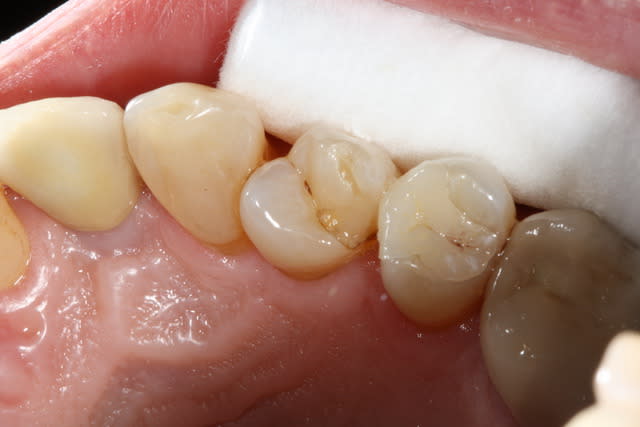

Puisque tout le monde montre des photos, à mon tour.

Il m'aura quand même fallu un petit moment avant de réussir à faire des onlay qui ressemble à quelque chose... Comme quoi, c'est pas que le prothésiste qui bosse!

Par contre me former ça commence à me coûter cher... Je ne fait presque plus de SPR50/SPR57...